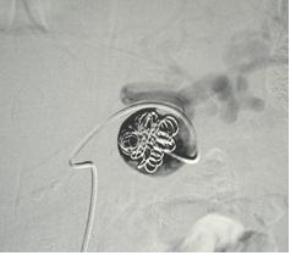

栓塞后弹簧栓子逸出至右肺静脉 |

栓塞后弹簧栓子逸出至右肺静脉 |

弹簧栓子在左心房“狂”跳 |

去哪儿啦? |

在这儿! |

嵌在股深浅动脉分叉处 |

弹簧栓子被移除 |

继续栓塞 |